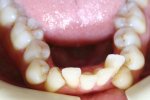

CLIII skeletal & dental; Severe crowding; Posterior and anterior cross-bites; “Peg laterals”; Bimaxillary dental alveolar protrusion. Extraction...

tongue thrust; case requires extraction of 2 teeth on mandible;

this case is treated similar to most cases using only the Brackets, wires and...